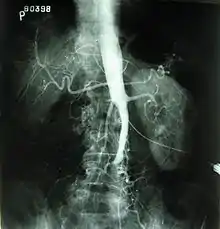

عادةً ما يُظهر الفحص البدني ضعفًا في نبضات الشريان الفخذي وانخفاضًا في المنسب الكاحلي-العضدي. يمكن التحقق من التشخيص عن طريق التصوير المضاعف الملون، والذي يكشف إما عن ذروة السرعة الانقباضية أكبر من أو تساوي 2.5 في موقع التضيق و/أو شكل موجة أحادية الطور. غالبًا ما يتم استخدام تصوير الأوعية بالرنين المغناطيسي (MRA) وتصوير الأوعية الطبقي المبرمج (CTA) لتحديد مدى ونوع الانسداد. يُمكن أيضًا استعمال طريقةٍ أُخرى وهي التصوير الوعائي بالطرح الرقمي [الإنجليزية] والذي يسمح بالتحقق من التشخيص وعلاج الأوعية الدموية في جلسةٍ واحدة.[1]

يوفر تصوير الأوعية معلومات مهمة فيما يتعلق بتروية وسلامة الشرايين البعيدة (مثل الشريان الفخذي). يعد وجود الشرايين الجانبية في منطقة الحوض والفخذ مهمًا في الحفاظ على تدفق الدم وحيوية الأطراف السفلية. ومع ذلك، يجب استخدام تصوير الأوعية الدموية فقط إذا كانت الأعراض تستدعي تدخلًا جراحيًا.[1]